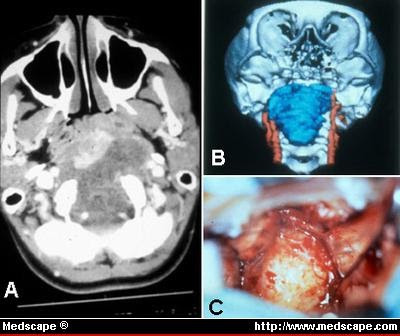

A Multidisciplinary Team Approach To Skull Base Chordomas In Journal Of Neurosurgery Volume 95 Issue 2 2001

A Multidisciplinary Team Approach To Skull Base Chordomas In Journal Of Neurosurgery Volume 95 Issue 2 2001 from thejns.org